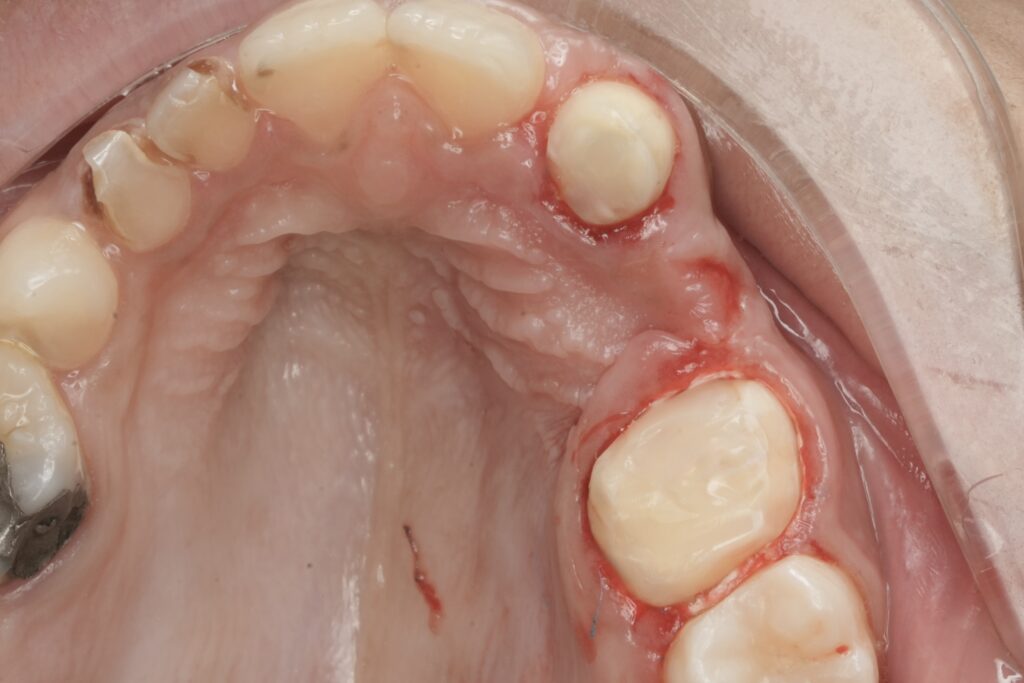

Management of the Ill-Fitting Canine Crown

Within the same isolation field, the canine crown was evaluated. Marginal discrepancies and biological width concerns were evident. The crown was removed, allowing direct assessment of the underlying tooth structure and margins.

This step was critical, as untreated coronal leakage or prosthetic misfit can compromise even the most meticulously executed endodontic treatment. A provisional plan was established to restore proper marginal integrity and periodontal health before definitive prosthetic replacement.